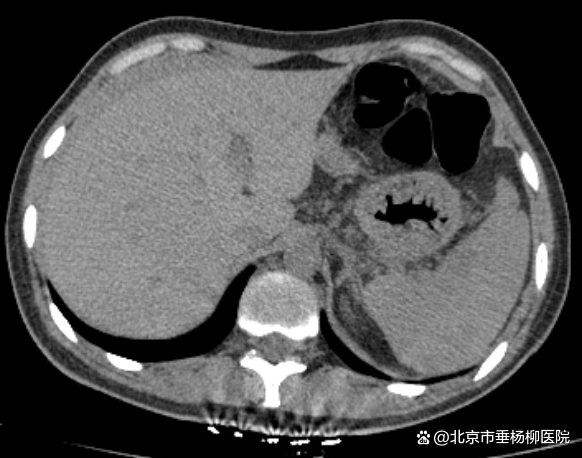

检查结果回报,血常规提示血色素94g/L轻度下降,急诊B超显示肝周可见低密度影。立即联系普外科,用平车将患者送去行腹部CT检查,放射科报告危急值:发现脾脏密度不均,腹腔积液,考虑脾破裂。普外科立即给患者办理入院手续,郭春海及任杰医生加班为患者行急诊腹腔镜探查手术,术中见腹盆腔内大量积血及血凝块,脾脏下极破裂,行脾修补术及自体血回输。术后患者病情稳定,顺利出院。

▲腹部CT提示脾脏密度不均,肝周积液,考虑脾破裂